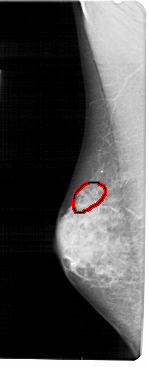

FILE: A_1937_1.LEFT_MLO.OVERLAY

TOTAL_ABNORMALITIES 1

ABNORMALITY 1

LESION_TYPE CALCIFICATION TYPE PLEOMORPHIC DISTRIBUTION CLUSTERED

ASSESSMENT 4

SUBTLETY 3

PATHOLOGY BENIGN

TOTAL_OUTLINES 1

LEFT_MLO LINES 5491 PIXELS_PER_LINE 2221 BITS_PER_PIXEL 12 RESOLUTION 43.5 OVERLAY